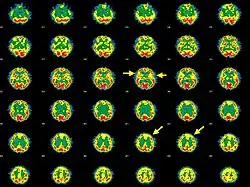

Brain SPECT transaxial images of a patient afflicted with Hashimoto's encephalopathy showing cerebral hypoperfusion in the left frontal lobe and in both temporal lobes (arrows). | |

- Single photon emission computed tomography shows focal and global hypoperfusion (75% of cases)